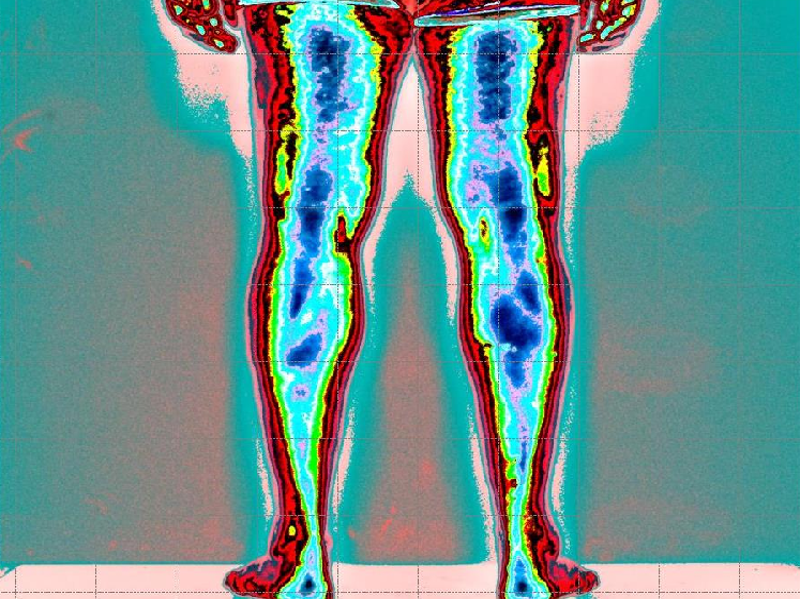

Nella foto si evince assenza di attivazione muscolare degli arti inferiore (colore rosso)

Ipertono della tensione muscolare (colore blu scuro) a compenso della catena anteriore.

Prima, minima tensione muscolatura posteriore del tronco è arti inferiori.

Forte tensione muscolatura glutei a compensare.

Leggenda: colore rosso inattivazione tensione muscolare

Verde, minima tensione muscolare

Azzurro normale tensione muscolare

Blu scuro, aumento della tensione muscolare